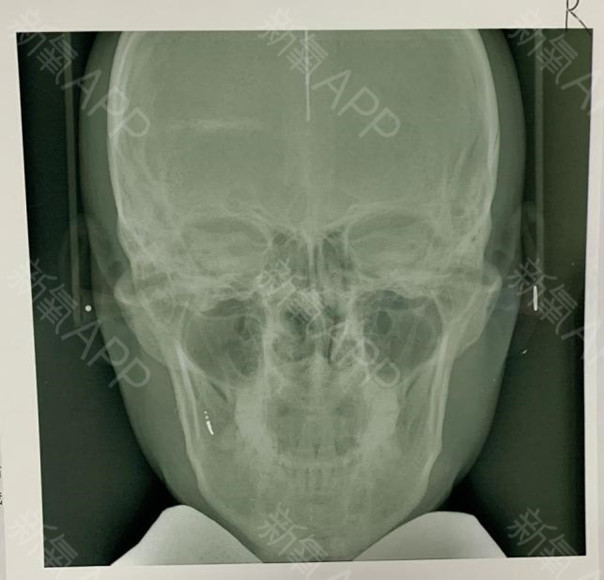

二、术前数据诊断:

鼻部形态无畸形,鼻梁低平,鼻背较宽,鼻头肥厚圆钝,鼻小柱稍短小,鼻部皮肤黏膜无红肿及破溃,副鼻窦区无压痛,下颏短小稍后缩,口腔黏膜无红肿及破溃。

1、低鼻症

2、宽鼻症

3、小颏症